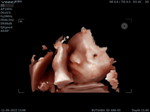

ท้อง5เดือนแล้วแต้ยังไม่รู้สึกว่าลูกดิ้นเลย ผิดปกติมั้ยคะ ท้องแรกกังวลจังเลยค่ะ

ท้องแรกจะรู้สึกช้าค่ะ แต่ก่อนนอนแม่ลองนอนสบายๆ แล้วแตะๆสังเกตที่ท้องดูนะคะ